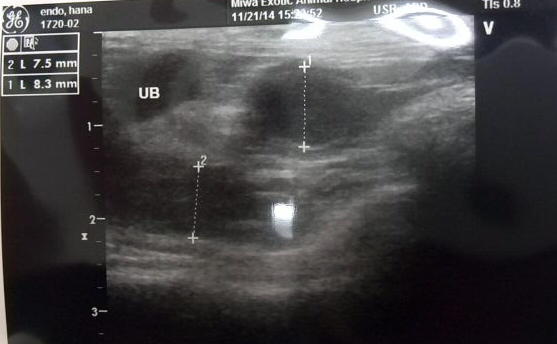

はなちゃん通院再び二回目 前回いってから、尿検査、尿試験紙で状態を見る事を経て 子宮に疑いがあるということで、本日は麻酔をしていろいろ検査する事に。 血尿は一日おきにでたりでなかったりだったようで、尿採取して検査にまわして 貰った時の分にはほぼでてなかったよう。 検査の結果、膀胱には異常はみられないけれども子宮疾患の疑いありとのこと。 来週手術して子宮をとることになりました。 子供生むこともないので、懸念個所を取り除けば他の部分には問題が転移しないのなら 早めの処置をしましょうということで。 血尿として血が出てしまっているし、少し貧血気味になりつつあるという検査結果も出たし このまま弱ってからの手術よりも元気なうちに、年齢も3歳半くらいで、 はなちゃんの体力にかけるかんじです。 私の個人的な方針で、4歳越したら手術はせず、薬治療であとは自然に任せるって 決めているので、はなちゃんもそんなかんじで。 先生の説明では、子宮除去手術はいわゆる去勢手術と同じかんじで、 小動物は手術そのものよりも麻酔のリスクが高いそうな。 今回のような案件だと、犬猫なら発覚即手術も普通らしいけど、 はなちゃんは今日も麻酔したし、またすぐというのは心配というのもあって 1週間家で落ち着かせて様子を見つつ、来週手術ということに。 検査結果の詳しい数値の書いてある紙もいただいたんですけど、 ヘマトクリットが30で少なめでという説明以外はハリ基準値内だったみたい。 用紙がフェレット用だったので、そのあたり誤解があると困るかもしれないので 載せませんけど。 今回のはなちゃんのレントゲン写真とエコー写真 レントゲンは2枚 お腹にガスがたまってるのと、心臓が少し大きいのが気になる個所 心臓が大きいのは疾患というより麻酔が覚めてきているときに すこし心拍が弱くなったので補助的な処置をしたとのことで その辺り原因じゃないかという話。 麻酔は今回初めてなのですが、次も同じようになってしまうのではの懸念には なんかかのたんのお骨でも思ったけど、骨でも個別にわかるもんだな…って あ、はなちゃんだーって思えるのがすごい。 UBっていうのが膀胱で、そこには問題なし、その上の白い波線が入ってるのが 子宮の問題個所で、そこからの出血の可能性、ということ。 あくまで可能性ということではあるけど、だからって様子見しすぎて 貧血ひどくなって手術も無理って事になったら検査の意味ないしってことで 手術にふみきるわけです。 体重353g 今回の明細 再診料A 864 皮下点滴(6-10m1)1620 尿一般検査(試験紙、沈渣) 1620 採血料B 2700 CBC(哺乳類) 1836 生化学検査基本5項目 3240 X線検査 2画像 5940 超音波断層検査 3780 ガス麻酔B・短時間処置 5400 内服薬 1663 合計 28663 円 |